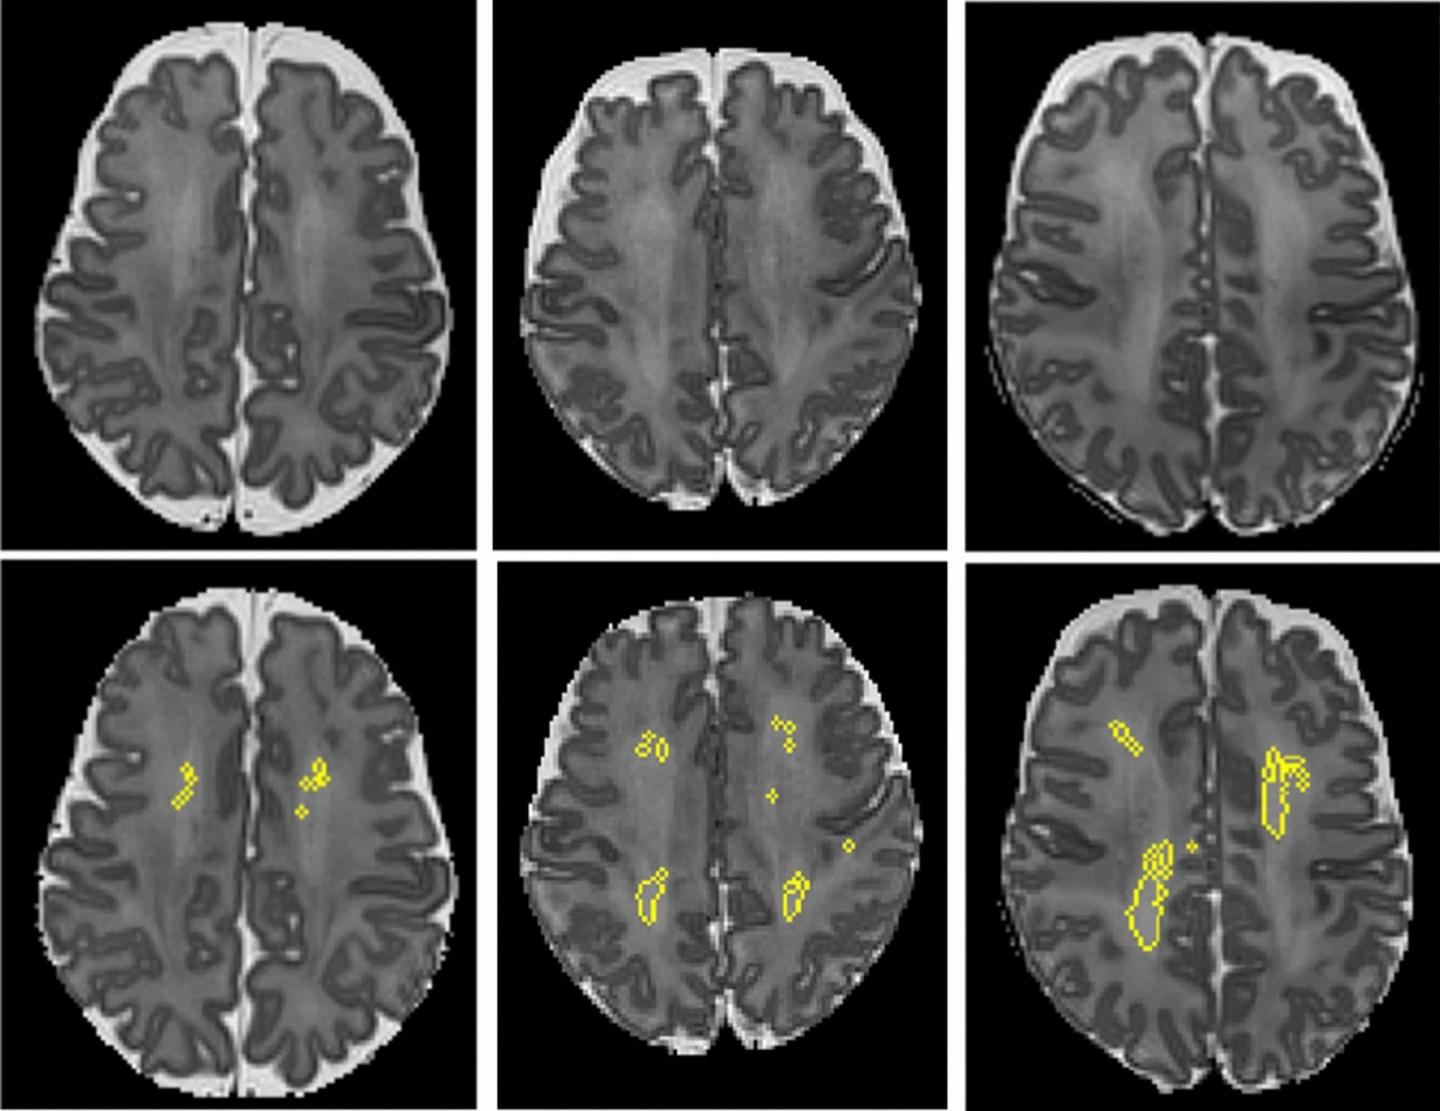

image: These MRI scans show diffuse white matter abnormality (DWMA). The top three panels display raw MRI images from very preterm infants born at 27 weeks (left), 26 weeks (center) and 31 weeks (right) gestation. Higher signal intensity can be seen in the central white matter, particularly for the 31-week gestation infant. The bottom panels display the corresponding slices with objectively segmented DWMA in yellow. The 27-week infant (left) was diagnosed with mild DWMA, the 26-week infant (center) was diagnosed with moderate DWMA, and the 31-week infant had severe DWMA.

Cincinnati Children's and Nature Scientific Reports